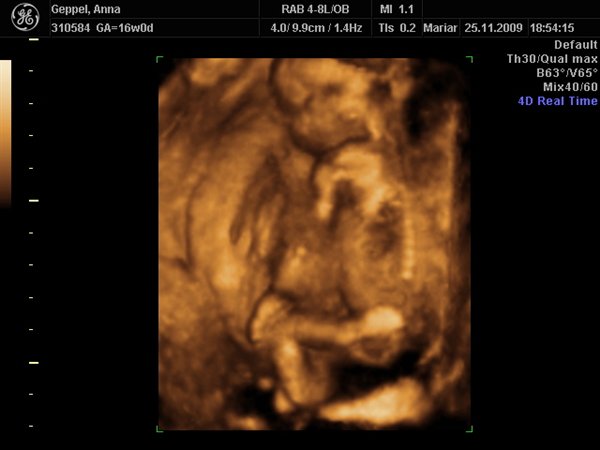

Det første var det bedste der blev taget i 3D, da det er svært at få gode 3D billeder allerede i uge 17! Synes han ser nuttet ud med sin lille opstoppernæse